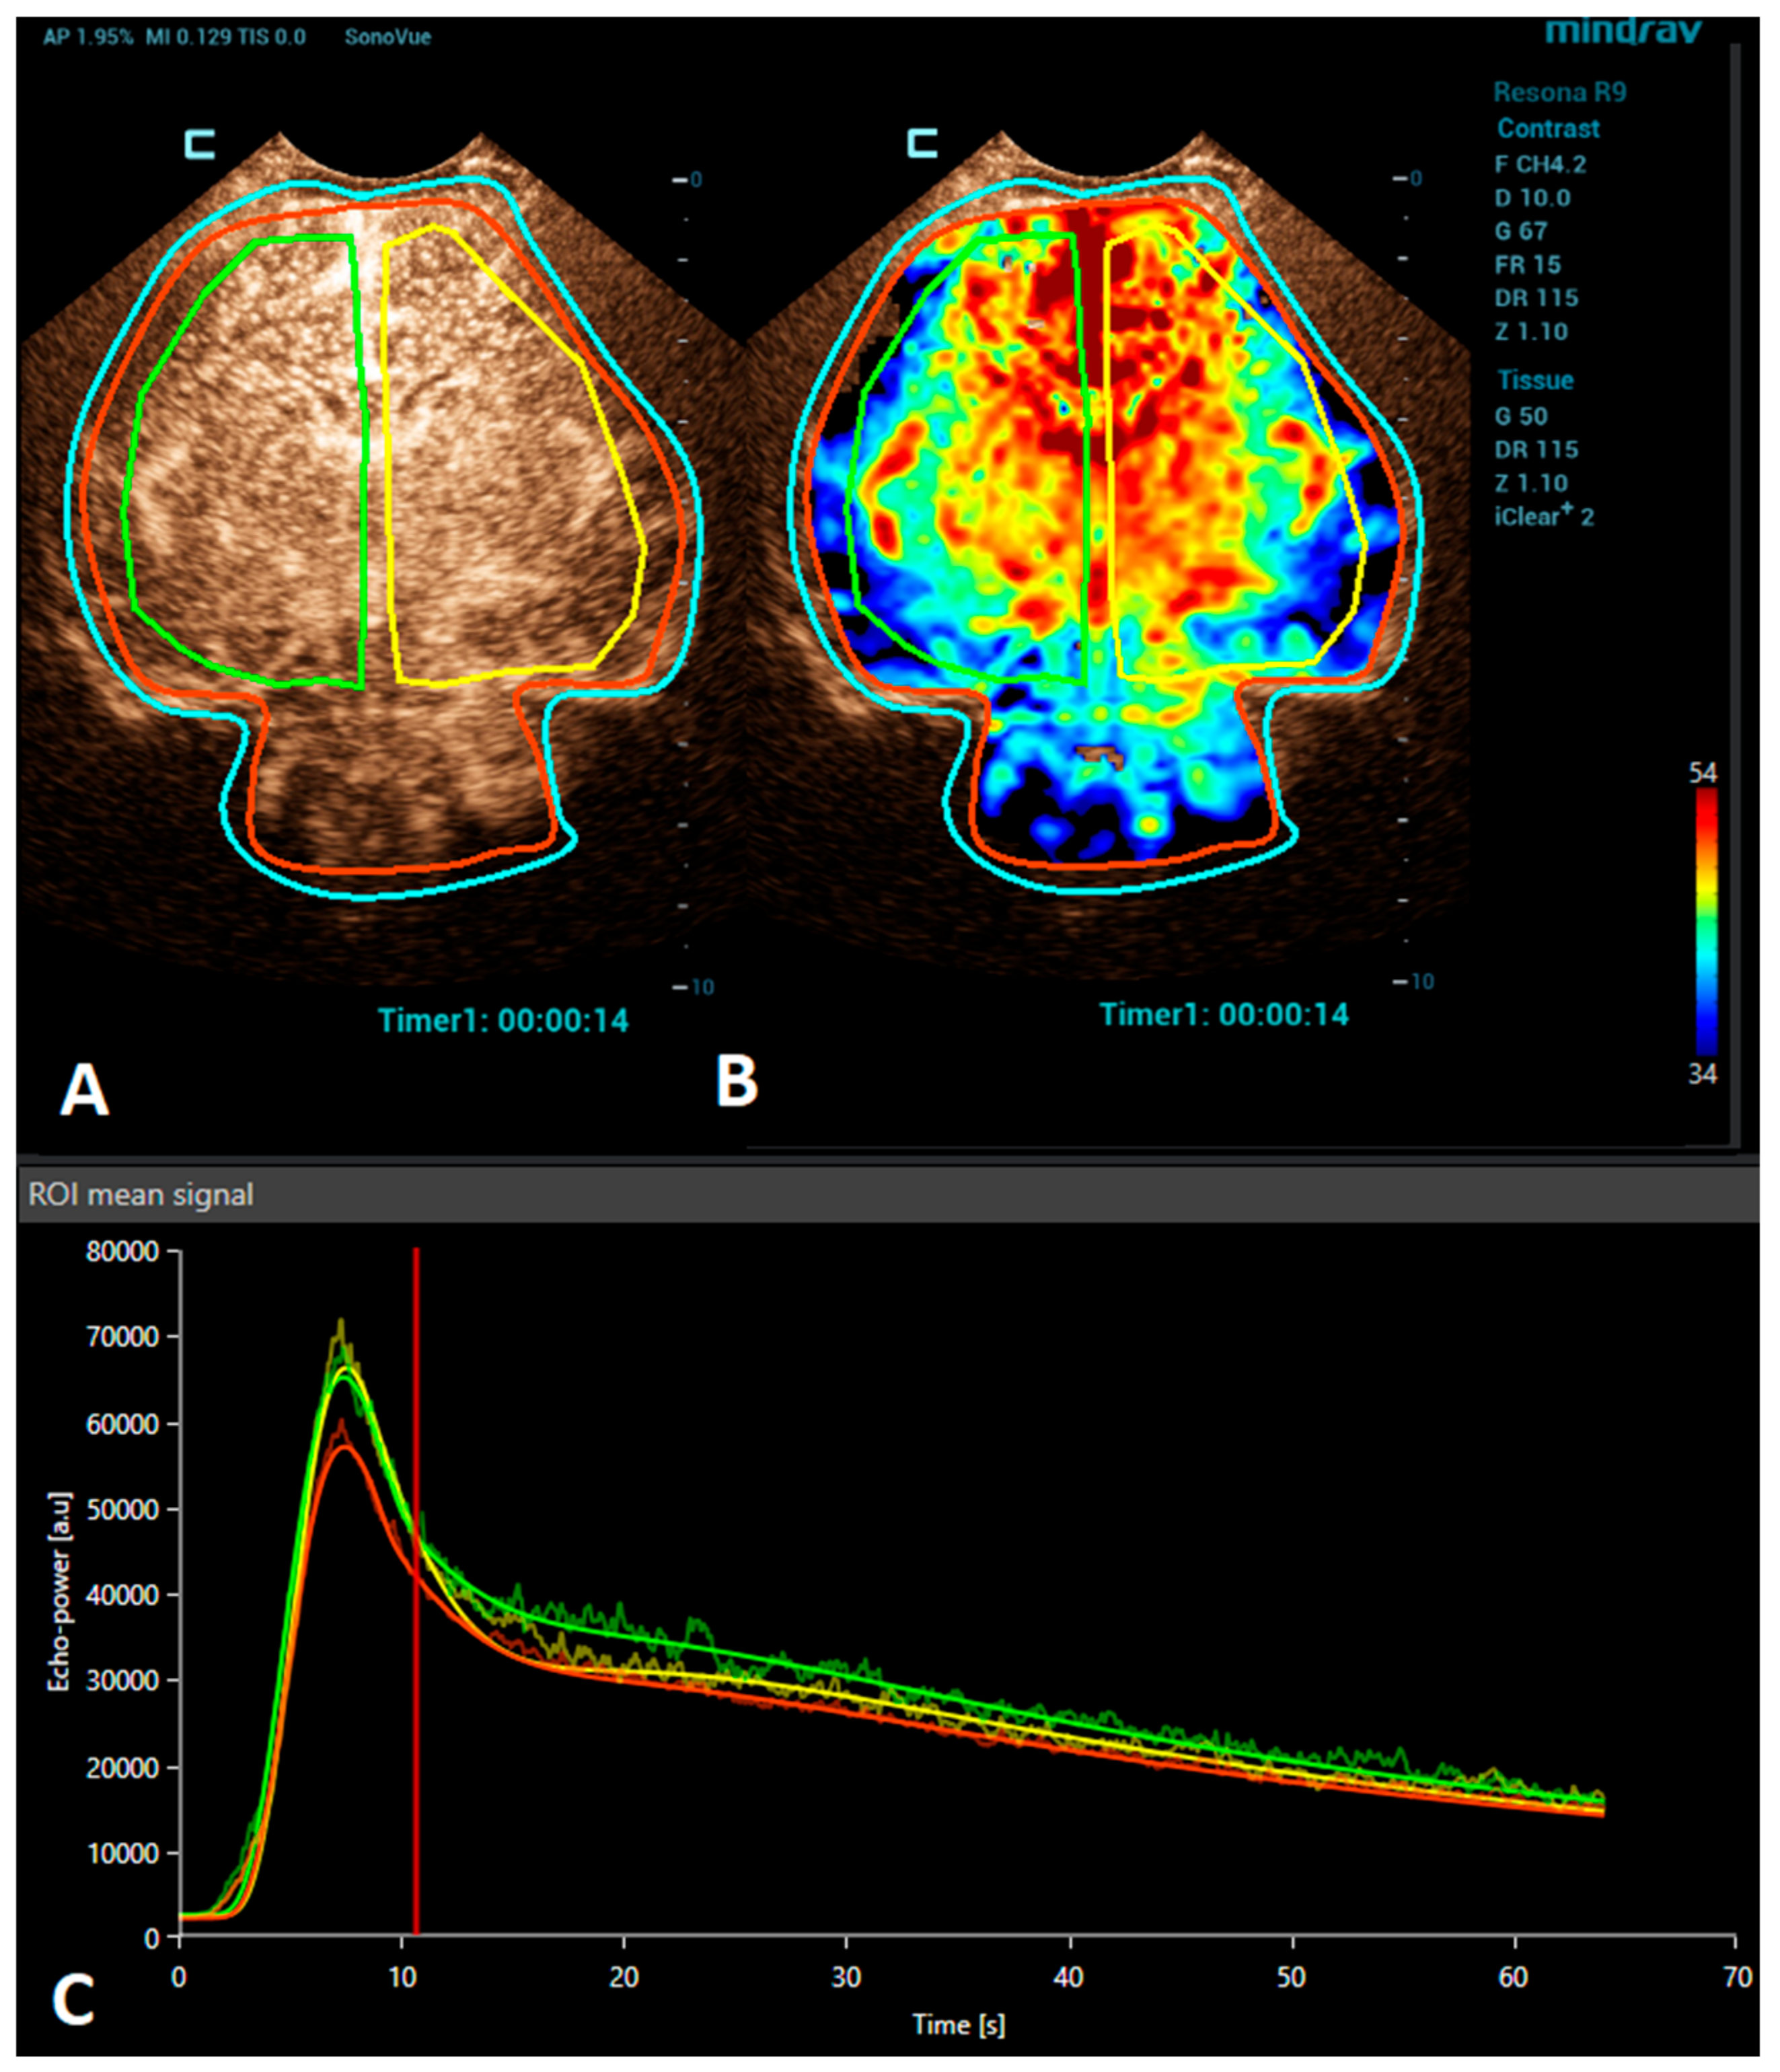

Figure 1.

A VueBox® analysis of a 4-day-old premature girl with neonatal sepsis and normal symmetric CEUS brain perfusion. Regions of interest were set for: the whole brain/both hemispheres (red), right hemisphere (green), and left hemisphere (yellow). (A) The above-left panel displays a coronal CEUS image, demonstrating symmetric brain perfusion during the arterial phase of enhancement. (B) The above-right panel shows a normal symmetric coronal perfusion map of the average contrast signal intensity (MeanLin) parameter. (C) The below panel presents time–intensity curves for the right hemisphere (green) and left hemisphere (yellow) and the whole brain (red). A subsequent brain MRI scan was normal.

Brain CEUS is a promising diagnostic tool that may have advantages in comparison to MRI. Due to its bedside nature, it can be performed at any time, even during therapeutic hypothermia in an intensive care unit. Therefore, it may be used to diagnose HIE earlier and also allow monitoring the patient’s response to the treatment. The ability of CEUSs to visualize the microvasculature and evaluate brain perfusion in real time means that it has great potential to become a valuable diagnostic tool in the evaluation of HIE. There are many studies reporting the use of CEUSs for the assessment of HIE [9,24,37,38]. Recently, a quantitative CEUS approach has been introduced to screen for the presence of HIE [24]. In this study, infants with HIE were distinguished from unaffected infants by assessing the ratio of basal ganglia to cortical perfusion using wash-in, peak enhancement, and area-under-the-curve kinetic parameters on a time–intensity curve. Another recent study demonstrated that alterations in the CEUS wash-out perfusion parameters can be observed in the presence of a hypoxic-ischemic injury [38]. Future research with larger cohorts is needed to validate the diagnostic utility and prognostic value of CEUS in HIE cases. In addition, the establishment of a large CEUS database with normal brain perfusion parameters are also necessary (Figure 1).